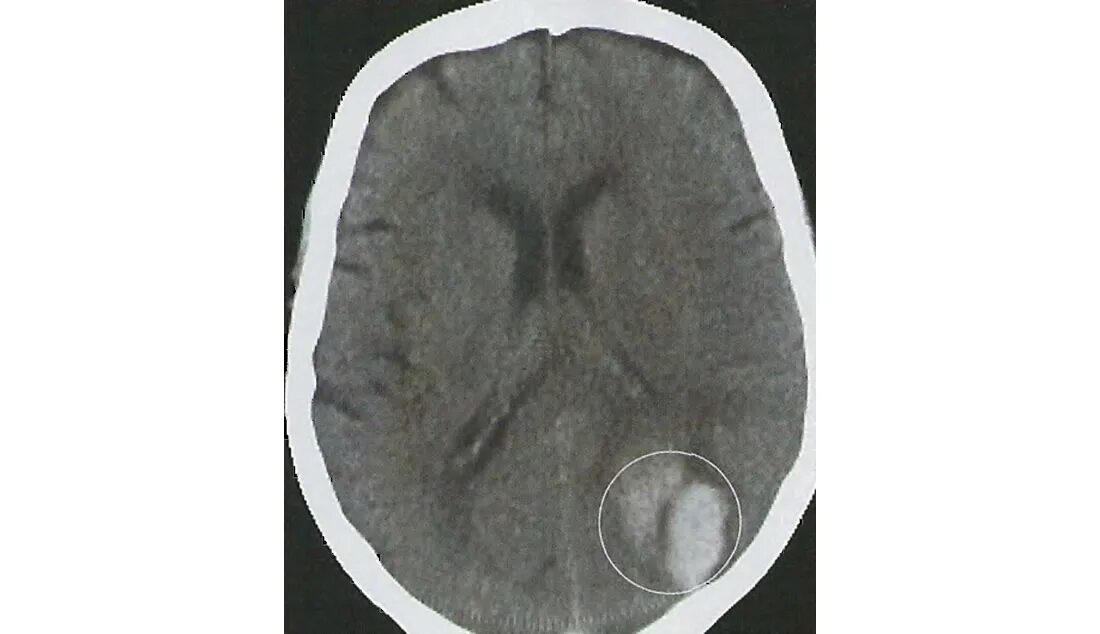

Кровоизлияние в мозг у новорожденного степени